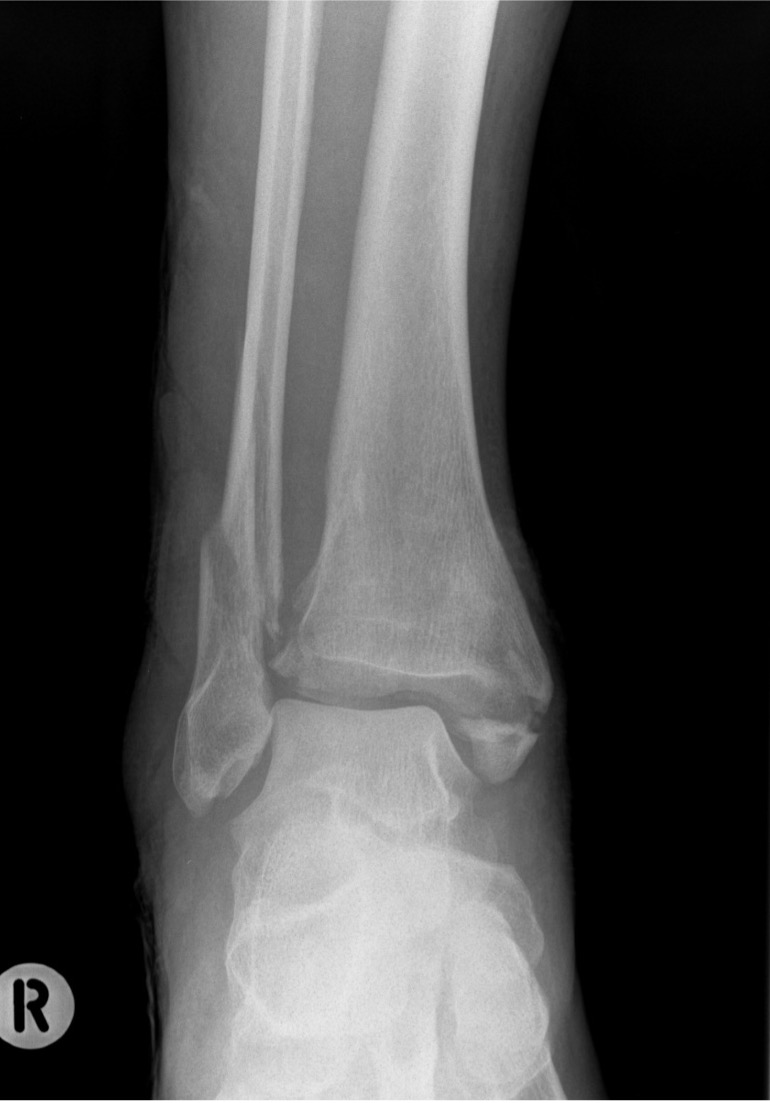

X-ray assessment

3 standard views

AP / Lateral / Mortise

Increased tibio-fibular clear space  Overlap Increased medial clear space

Medial border of the fibula

Lateral border of the posterior tibia (incisura fibularis)

Measured 1 cm above the plafond

Overlap of the fibula and the anterior tibial tubercle

Medial talus to lateral medial malleolus

<5mm AP and mortise

> 6 mm AP view

> 1 mm mortise view

< 4mm

Equal to superior clear space

Syndesmotic injury Syndesmotic injury

Deltoid ligament injury

Lateral talar shift

Ankle AP Xray Syndesmotic Measurements Ankle Mortice Xray Syndesmotic Measurements Mortise

Lateral talar shift / increased medial clear space / deltoid ligament injury

Ankle Fracture Increased Medial Clear SpaceAnkle Fracture Increased Medial Clear Space 2Maisonnerve

Tibia / fibular overlap < 1mm / syndesmotic injury

Ankle Fracture Syndesmosis WidenedAnkle Diastasis